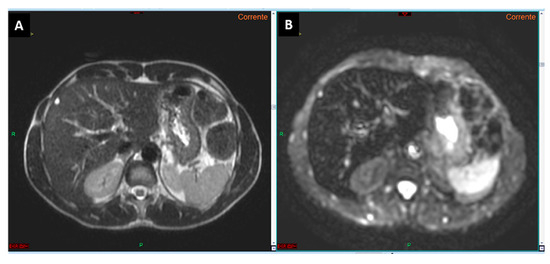

Figure 5.

CT images in the arterial (A) and delayed (B) phases show a lesion in the segment III in a cirrhotic liver (arrows in (A,B)), which cannot be accurately characterized as HCC according to EASL guidelines. In the MRI study with a hepatospecific contrast agent (arrows in (C–H)), the lesion exhibits typical features of HCC according to EASL guidelines: arterial phase hyperenhancement (F) associated with contrast media wash-out in the venous phase (G). The lesion also demonstrates additional malignant features, such as signal restriction on diffusion-weighted imaging at b-value 800 (E) and hypointensity in the hepatobiliary phase (H). According to Jiang et al. (see reference no. [31], the lesion shows homogeneous intratumoral fat, as evident from the uniform signal drop in the T1 out-of-phase sequence (C) compared to the T1 in-phase sequence (D): this feature suggests a more favorable prognosis.